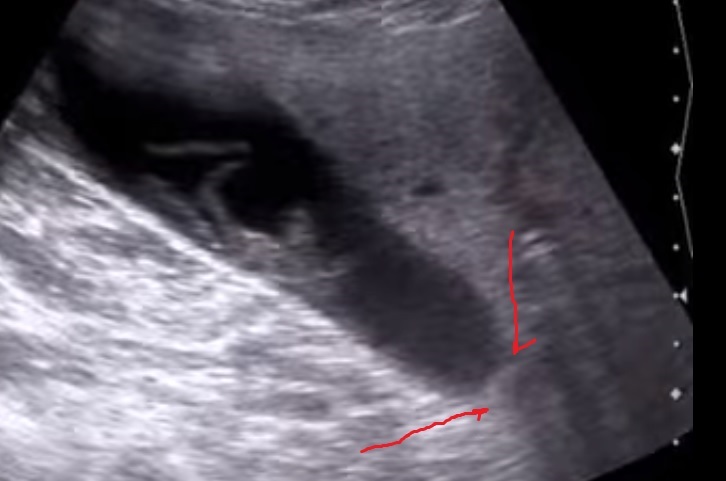

Нарисуйте нам на кадре из клипа.

Вложения

Безымянный.jpg

Ни на видео, ни в кадре - нигде не видно блокирующего конкремента.

Более того, нет "железных" признаков блока и гипертензии.

есть информация по случаю - флегмонозный холецистит, с формированием парапузырного инфильтрата, конкремент вклиненный в гартманов карман и пузырный проток Мирризи 1